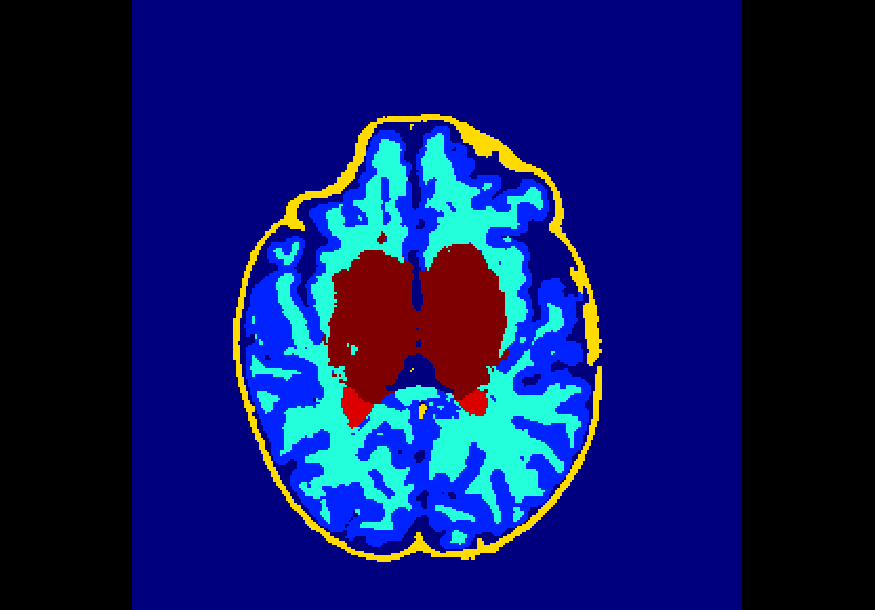

The dataset consisted of 70 3D T2-weighted brain MRI scans publicly available from the dHCP neonatal cohort. The segmentation maps had 10 classes, corresponding to: zero-pixel background, cerebrospinal fluid (CSF), cortical grey matter (cGM), white matter (WM), background bordering brain tissues, ventricles, cerebellum, deep grey matter (dGM), brainstem, and hippocampus. The scans covered an age range of 24.3-42.2 weeks. The data was available in NIfTI format; Figure 1 shows an example scan and corresponding tissue labels. We carried out a pre-processing step where each scan was independently normalised to zero-mean and unit-variance.

Finally, Table 4 shows that the model trained on data injected with different degrees of both Gaussian and salt-and-pepper noise (gaus01, gaus03, gaus04 with = 1, 3, 4 ; snp01, snp05, snp10 with prob = 0.01, 0.05, 0.10) achieves the best overall robustness across the 16 versions of the test set, where even the heaviest filtered images had very few segmentation inaccuracies. For instance, this model demonstrated high levels of robustness on all 10 classes for noise-free data, on data injected with a previously unseen degree of salt-and-pepper noise (e.g. DSCs of 88%-99% on snp20), as well as on data with a previously unseen degree of Gaussian noise (e.g. DSCs of 72%-98% on gaus05). To illustrate, Figure 5 shows examples of the predicted segmentation of the model on the heaviest transformed images of the three filter categories used in these experiments. From the figure it is clear that the model achieved excellent mapping of the brain tissue regions. This shows a tremendous improvement from the baseline model which was trained using a conventional, noise-free approach and thus failed severely on the heavily corrupted images (e.g. DSCs of 0% for all 10 classes on snp20, see Table 2).